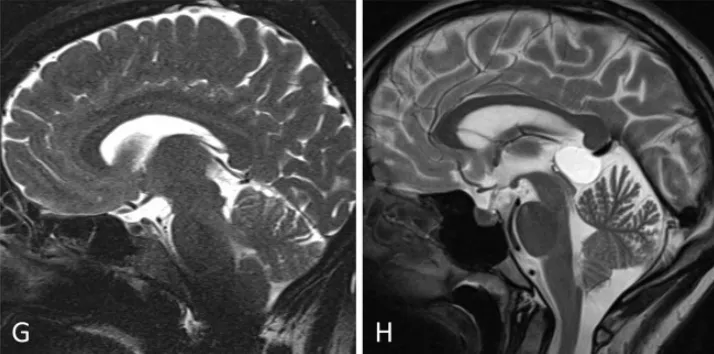

小脑幕倾斜度变异分析:旁正中入路(G)至松果体区的视角轨迹较中线入路(H)更为平缓。